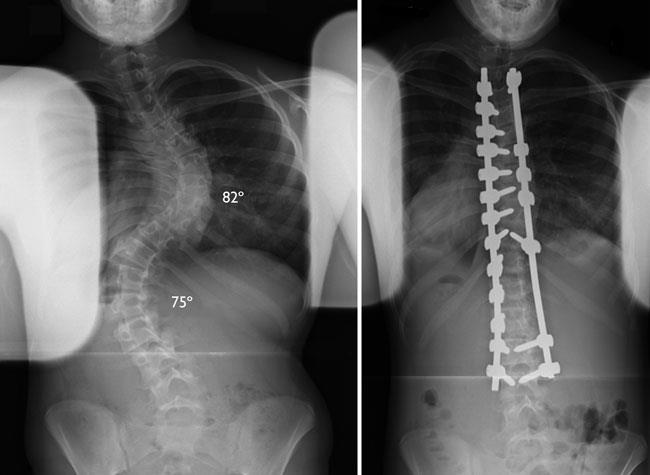

Esta radiografía de la escoliosis de un paciente mide 82° en la curva superior y 75° en la curva inferior.

Esta es una radiografía del mismo paciente que se muestra en la radiografía de arriba, pero con el implante usado para corregir la escoliosis.